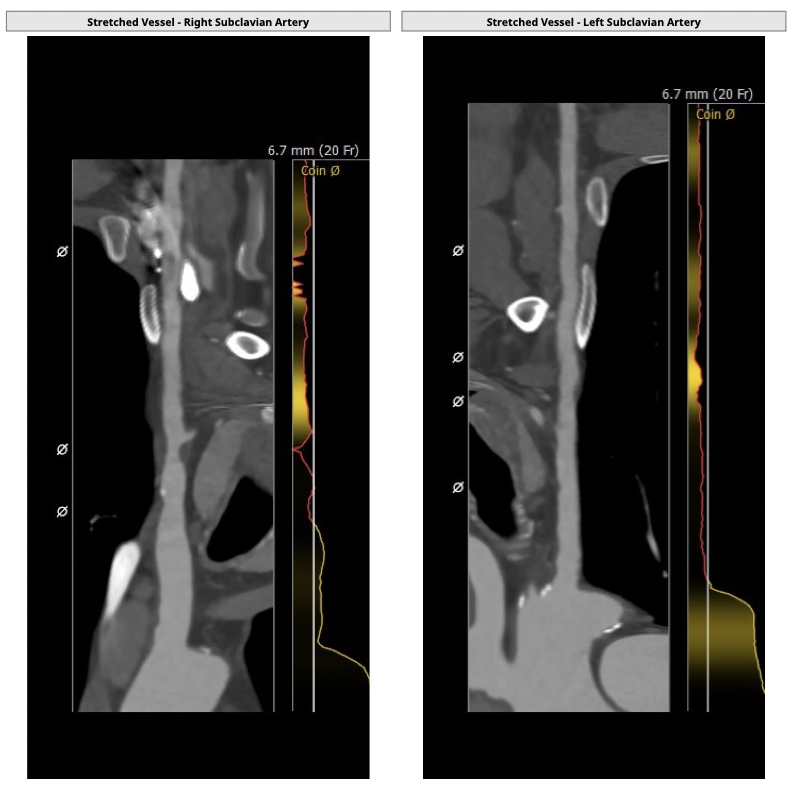

①患者因规律透析导致钙磷代谢紊乱,外周血管斑块钙化严重,最狭窄处仅2.8mm,通路建立难度极大(左右颈动脉均不符合入路条件);

确保冠脉安全,拟采取PCI+TAVR一站式手术策略,因患者右侧股动脉钙化严重、入路狭窄,拟采取无鞘法从右股动脉穿刺入路,选用20mm球囊预扩、L23号VenusA-Valve瓣膜、采用VenusA-Plus输送系统确保瓣膜的精确释放,瓣膜释放后结合造影和超声情况,决定是否后扩。